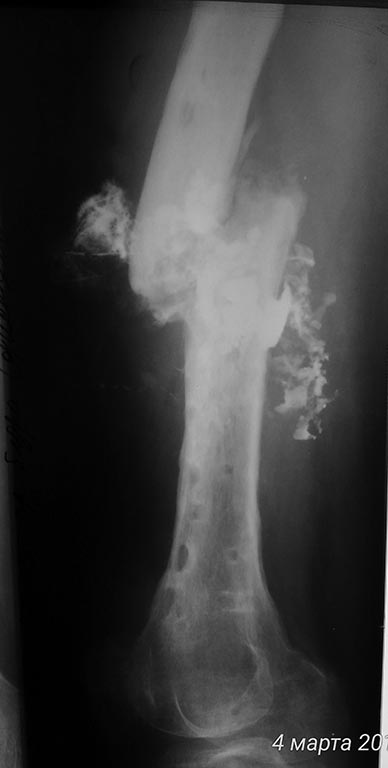

Помогите, пожалуйста, определиться с объёмом и методом оперативного вмешательства. Больной К., 1983 г.р. попал ко мне (в отделение гн.хирургии) 02.03.17. Краткий анамнез (со слов больного и согласно предоставленной мед.документации): 2013г - о/перелом ср/3 правой бедренной кости. АВФ. Затем конверсия на БИОС. В позднем послеоперационном периоде - нагноение.

Диагностирован ХТО средней трети правого бедра, свищевая форма.

2014г - удаление м/к, некрэктомия, стержневой АВФ. 2015г - рецидив. Повторная СНЭ, сегментарная резекция с\3 правой бедренной кости, пермонтаж АВФ.

Сентябрь 2016г - демонтаж АВФ. Больной ходил с полной опорой, в бандаже. В середине феврале 2017 обострение процесса, выраженный отек правого бедра, лихорадка. Пациент самостоятельно дренирует очаг.

Локально при поступлении: по латеральной пов-ти ср/3 правого бедра п/о рубцы, 2 свища с гнойно-геморрагическим отделяемым, дно - бедренная кость. На рентгенограмме: перелом не сросся. Выполнена фистулография.

Дополняю рентген архив

Прокомментирую:

самый первый снимок от 12.2016

Последние от 02.2017.

По рентгенограммам - тотальный остеомиелит бедренной кости. Для подтверждения можно сделать спиральную КТ. В Советское время выполнялись трепанации кости, долговременные активные промывные системы, эндостальное облучение кости лазером и т. п. Длительный постельный режим, огромный расход биологически активных препаратов, непрерывный врачебный уход... И это только для санации очага. Если нет возможности тотального эндопротезирования, то ампутация. И, так - делают!